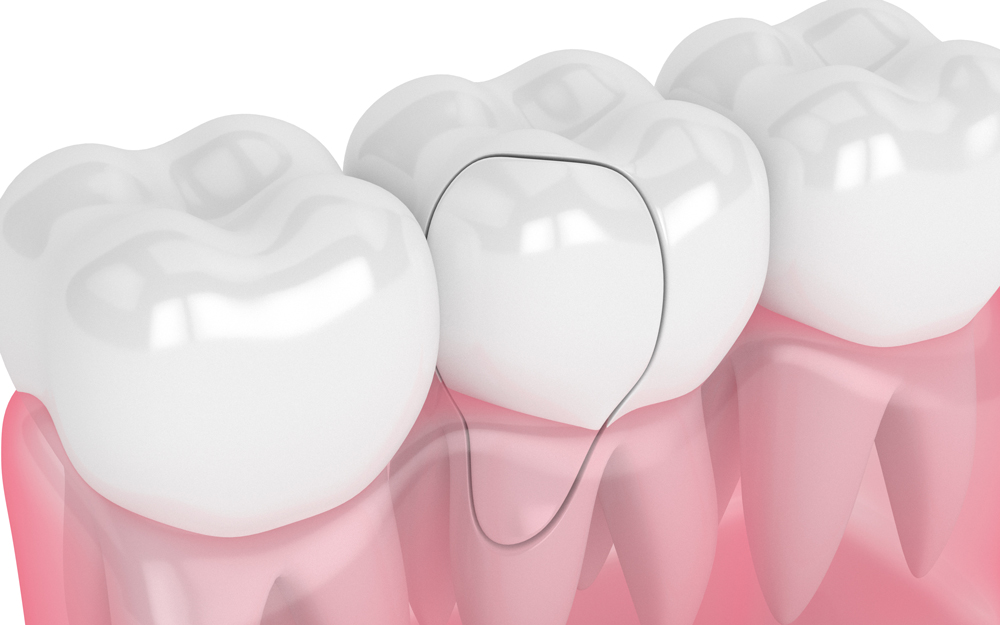

STEP 02. 교합면에서 잇몸 경계까지 균열

증상 : 씹을 때 찌릿한 통증이 있을 수 있습니다.

치료 : 치아가 쪼개지는 것을 막는 크라운 치료가

필수입니다. 필요한 경우 신경치료가

동반 되기도 합니다.

STEP 02. 교합면에서 잇몸 경계까지 진행된 균열

치료 : 치아가 쪼개지는 것을 막는 크라운 치료가 필수입니다.

필요한 경우 신경치료가 동반되기도 합니다.